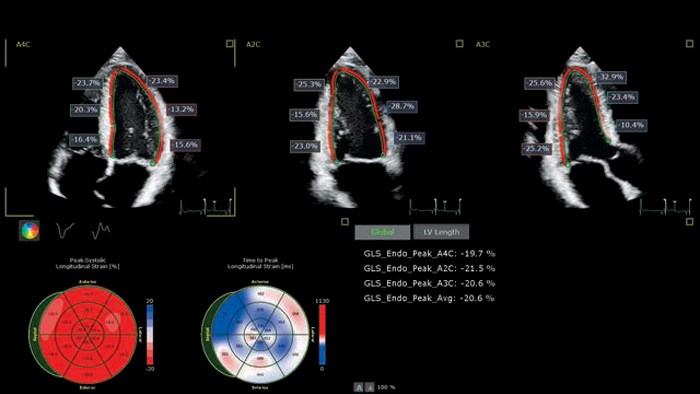

Dr. Teresa Lopez-Fernandez, La Paz University Hospital, Madrid, Spain

Using advanced ultrasound tools to assess CTRCD

Time-consuming methods are overcome by applying Philips Anatomically Intelligent Ultrasound (AIUS) to cardiotoxicity prevention.